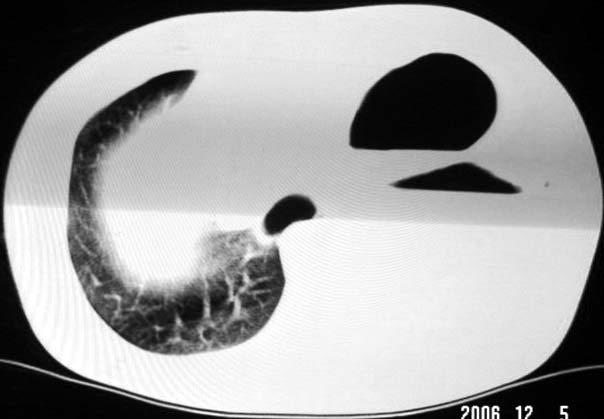

标题: CT5517:女性、24岁,反复胸痛、气促不能平卧半月。 [打印本页]

标题: CT5517:女性、24岁,反复胸痛、气促不能平卧半月。

左侧气液腔与胃腔影相连,考虑膈疝。钡餐检查有助于诊断。

我看这是膈疝,在纵隔窗第六\\七幅图像上可见胃粘膜影,再者可见两个腔影,这在液气胸是不会有的.

左侧气液腔与胃腔影相连,考虑膈疝。钡餐检查有助于诊断

左侧气液腔与胃腔影相连,考虑膈疝。口服urografin检查有助于诊断。